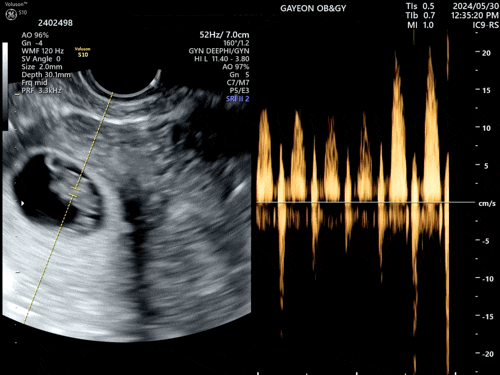

여러분, 저 엄마가 되었어요!

축하해 주세요? 짝꿍이랑 결혼 날짜 잡아놓고 나름 준비가 한창이던 5월. 여기서 말하는 우리의 결혼 준...